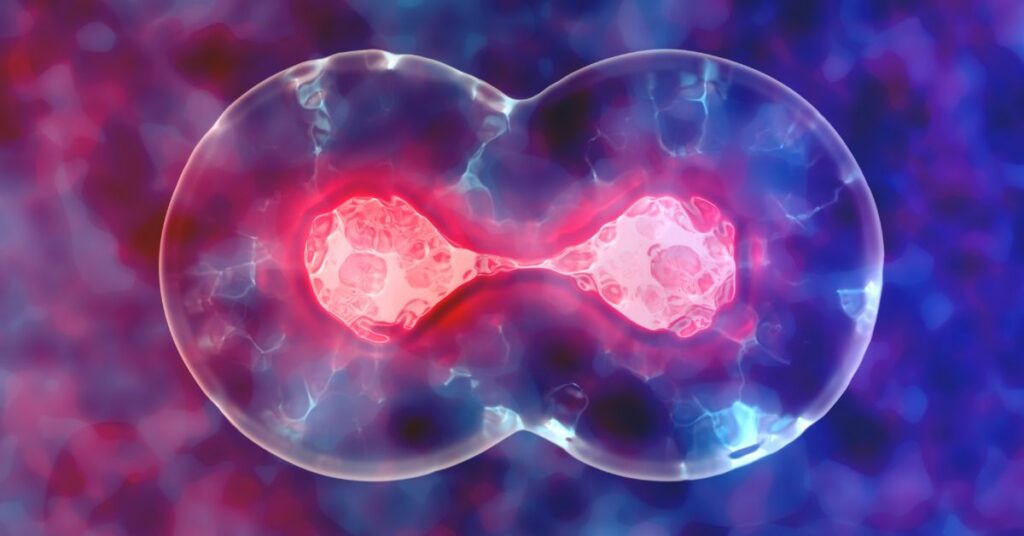

Sačuvajte matične ćelije svog deteta

Mnogi ne znaju koliko su dragocene matične ćelije, te da one imaju sposobnost umnožavanja i samoobnavljivanja. One danas, zahvaljujući naprednoj medicini, mogu da se koriste i za lečenje više od 85 bolesti. Zato su upravo vlastite matične ćelije pravo bogatstvo. Ako još imate dilemu da li treba da sačuvate matične ćelije iz pupčane vrpce vašeg bebca, saznajte sve što Vas zanima pozivom na besplatan info-centar vodećeg, nemačkog, biomedicinskog centra 0800/808-808.